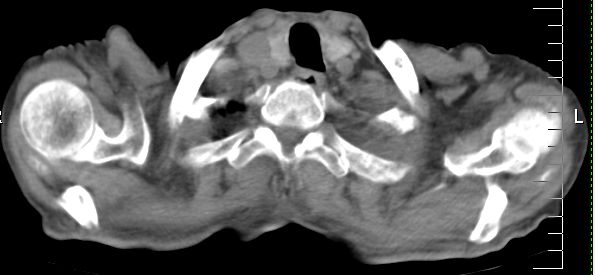

标题: CT10141:男、84岁,咳嗽、咯血1年。 [打印本页]

标题: CT10141:男、84岁,咳嗽、咯血1年。

左侧中心型肺癌,左侧胸腔积液部分包裹,心包积液,肿膈淋巴结显示。

咯血病史较长,左肺下叶实变,体积未明显缩小,隐约可见血管影及坏死阴影,双肺门及纵隔淋巴结增大,心包增厚积液,纵隔右移位,单侧胸腔积液,首先考虑:大叶型肺泡癌伴纵隔心包转移。